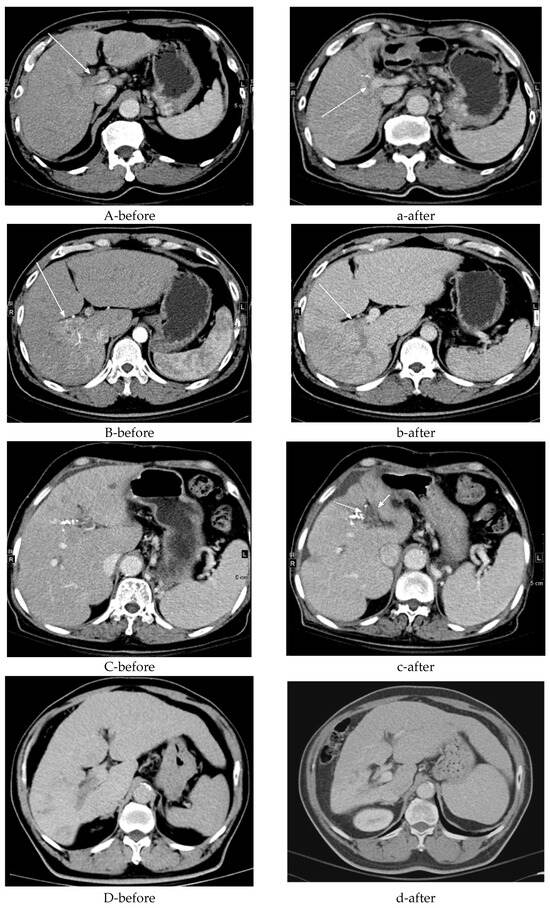

Imaging Features of Patients with Hepatocellular Carcinoma and Portal Vein Tumor Thrombosis Surviving Beyond 1 Year After Combined Therapy

Background/Objectives: Portal vein tumor thrombus (PVTT) is a severe complication of hepatocellular carcinoma (HCC) and is associated with poor outcomes. This study aimed to describe the imaging and clinical characteristics observed among HCC patients with PVTT who survived longer than one year following combined systemic therapy and radiotherapy. Methods: This retrospective, single-center study included 26 consecutive HCC patients with PVTT who survived more than one year after combined treatment. Baseline characteristics included PVTT extent classified according to the Liver Cancer Study Group of Japan—VP1 (segmental portal vein invasion), VP2 (second-order portal vein invasion), VP3 (first-order portal vein invasion), and VP4 (main portal trunk or contralateral PV invasion) and liver function assessed by Child–Pugh class and ALBI grade. Contrast-enhanced CT or MRI was evaluated at baseline and 6 months after treatment using RECIST 1.1 criteria. Results: The cohort was predominantly male (69%), and most patients had extensive PVTT (VP3–VP4, n = 19). Preserved liver function was common at baseline (Child–Pugh class A, n = 24; ALBI grade I, n = 14). Tumor response was observed in 23 patients (88%) during follow-up. Frequently observed post-treatment imaging findings included portal vein recanalization (n = 12), collateral circulation (present in 7 patients at baseline and 6 at follow-up), and compensatory liver hypertrophy (n = 6). Conclusions: Among HCC patients with PVTT who survived longer than one year after combined therapy, portal vein recanalization, collateral circulation, and compensatory liver hypertrophy were commonly observed imaging features. Given the retrospective design and survivor-selection nature of the study, these findings should be interpreted as descriptive observations rather than evidence of treatment efficacy or prognostic determinants. Full article

Show Figures

Figure 1